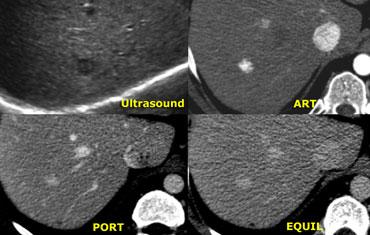

Hình ảnh siêu âm bên trái cho thấy hai tổn thương.

Tổn thương nhỏ (mũi tên xanh dương) có đặc điểm điển hình của u máu, trong khi tổn thương lớn hơn (mũi tên xanh lá) không đặc hiệu trên siêu âm.

Trên chuỗi xung T2W, u máu cho thấy tăng tín hiệu đồng nhất điển hình.

Tổn thương lớn hơn giảm tín hiệu nhẹ trên T1 và tăng tín hiệu nhẹ trên T2.

Ngấm thuốc gần như đồng nhất với các vách ngăn nhỏ không ngấm thuốc trong pha động mạch và có ngấm thuốc muộn (mũi tên vàng).

Chúng tôi cũng xếp loại tổn thương này là FNH.